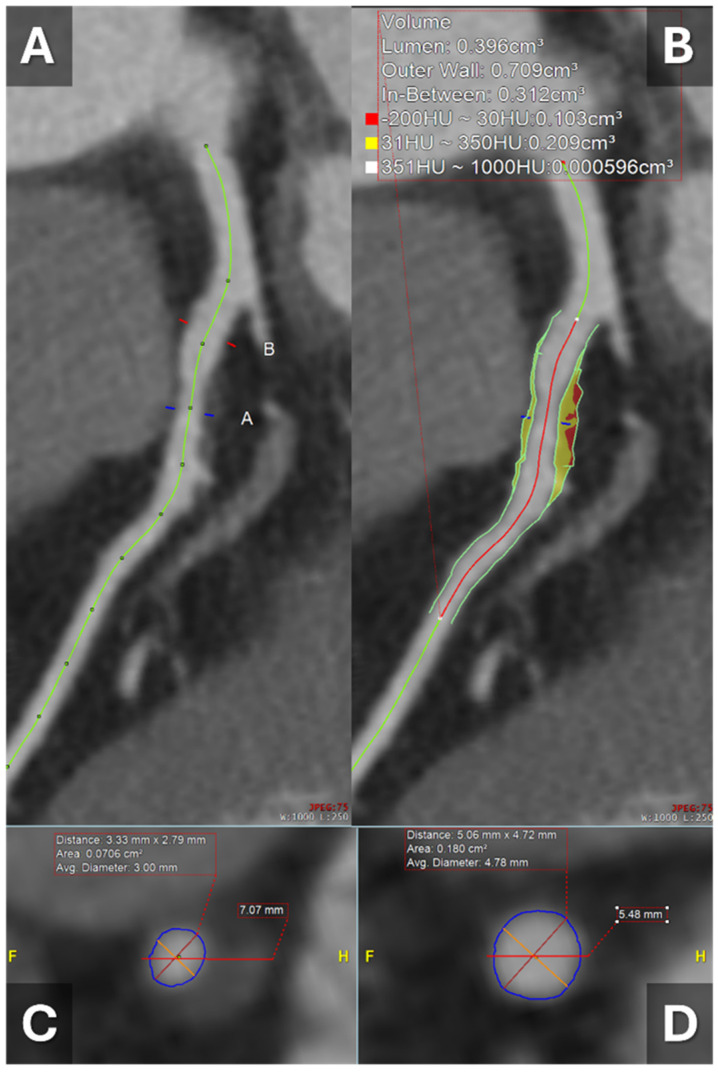

斑块成像技术的进步已经改变了心血管诊断,通过对动脉粥样硬化斑块的详细描述,超越了传统的狭窄评估。本文综述了不同模式的临床应用,包括双层光谱CT、光子计数CT、双能CT和CT衍生的分流储备(CT- ffr)。这些技术提高了冠状动脉病变的空间分辨率、组织分化和功能评估。此外,人工智能已经成为自动化斑块检测、量化负担和改进风险预测的强大工具。总的来说,这些创新为冠状动脉疾病的评估提供了更全面的方法,并支持个性化的管理策略。

Advances in plaque imaging have transformed cardiovascular diagnostics through detailed characterization of atherosclerotic plaques beyond traditional stenosis assessment. This review outlines the clinical applications of varying modalities, including dual-layer spectral CT, photon-counting CT, dual-energy CT, and CT-derived fractional flow reserve (CT-FFR). These technologies offer improved spatial resolution, tissue differentiation, and functional assessment of coronary lesions. Additionally, artificial intelligence has emerged as a powerful tool to automate plaque detection, quantify burden, and refine risk prediction. Collectively, these innovations provide a more comprehensive approach to coronary artery disease evaluation and support personalized management strategies.